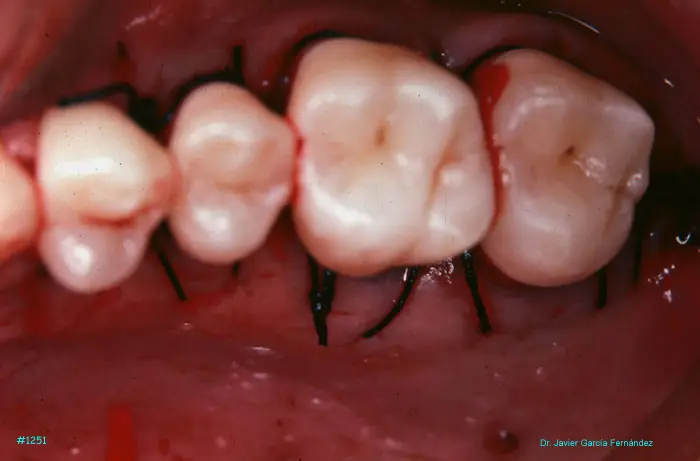

Atlas of Surgical Techniques in Periodontics. Chapter III. Atlas de Técnicas Quirúrgicas en Periodoncia